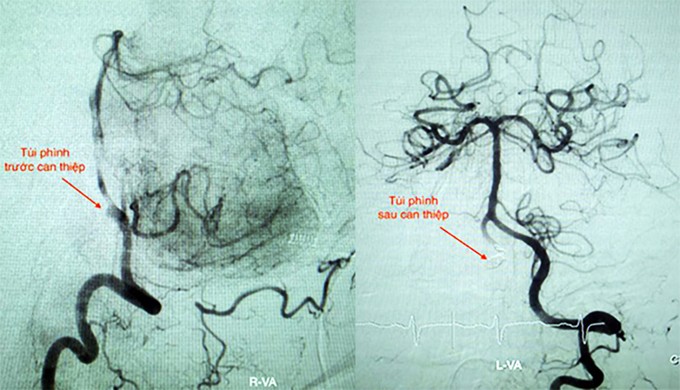

Các y bác sĩ cấp cứu, cho thở máy. Kết quả chụp CT não cho thấy bệnh nhân bị xuất huyết dưới nhện do vỡ túi phình động mạch đốt sống bên phải. Ê kíp can thiệp nội mạch mất hai giờ để sử dụng ba coil (vòng xoắn kim loại) làm bít túi phình, tái thông dòng máu.

Bác sĩ Hà Tấn Đức, Trưởng Đơn vị Can thiệp Đột quỵ bệnh viện, cho biết túi phình động mạch đốt sống là một bệnh lý hiếm gặp, chiếm khoảng 2% trường hợp túi phình trong não. Bệnh lý này có thể coi là sát thủ vô hình, vì khi có triệu chứng thì thường rất nặng do túi phình vỡ.

"Đây là một cấp cứu nội khoa, bắt buộc phải điều trị can thiệp càng sớm càng tốt nhằm loại bỏ phình mạch, ngăn chặn chảy máu tái phát do vỡ trở lại, hạn chế tử vong", bác sĩ Đức nói. Thả coil vào túi phình là phương pháp can thiệp hàng đầu thay thế phẫu thuật.